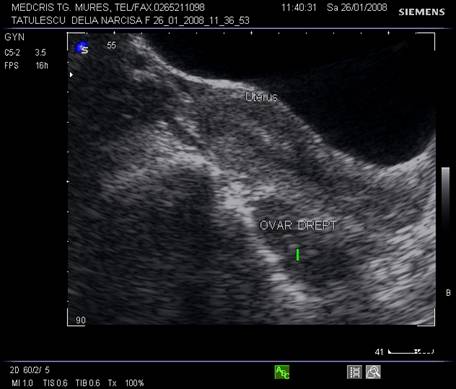

Ovarele. Sectiunea longitudinala directa, spre peretele lateral pelvin, la ecografia transvaginala, pune in evidenta ovarele cu forma elipsoidala. Acestea au structura ecografica relativ slab ecogena, in apropierea si sub vasele iliace.[5]

La pacientele care nu consuma contraceptive hormonale orale se pot identifica usor foliculii selectati preovulator sau corpul galben.

Marimea ovarelor: inainte de menopauza aproximativ 3,5 x 2,5 x 1,5 cm si aproximativ 2,0 x 1,5 x 1 cm dupa menopauza. Nu se poate aprecia volumul ovarian decat masurand cele trei diametre in planuri sagitale, oblice si coronale ale pelvisului.[1,2,9]

Fig. Nr. 360.Ovar sub vasele iliace , in ziua a XXI a de ciclu menstrual